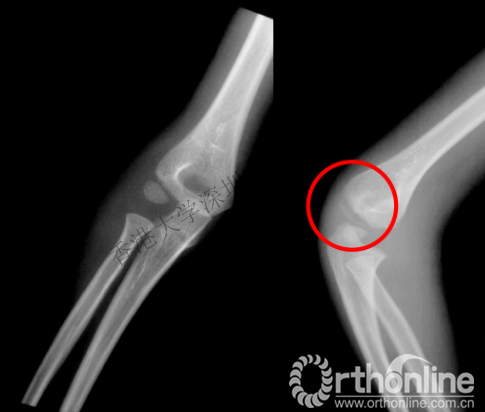

女,4岁,跌伤致右肘疼痛,X片示右肱骨外髁骨折。因肱骨外髁处软骨较多,骨折极易漏诊。

术中X片

因此,认识到在x片中,很多儿童的骨骺部分是软骨,并不能充分显像,选择合适的辅助检查,在治疗过程中需要考虑儿童的成长,做出正确的诊断,就显得尤为重要。